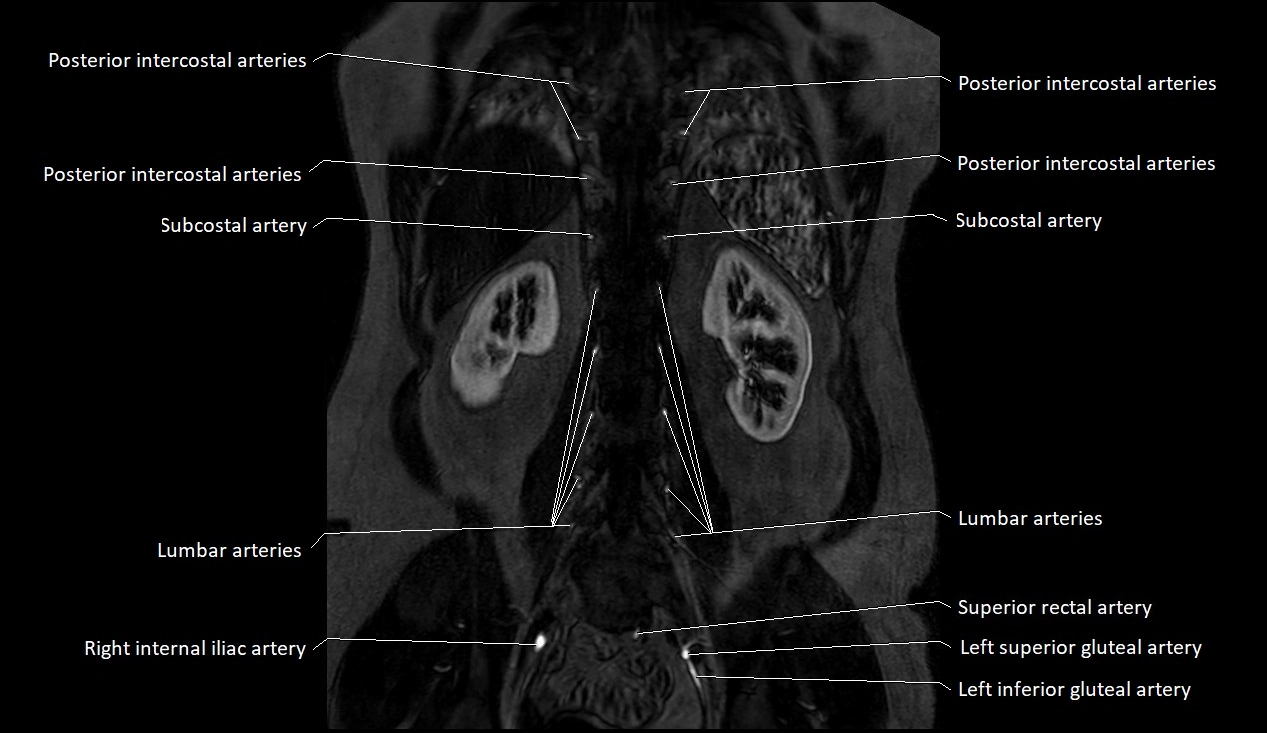

MRI images

image